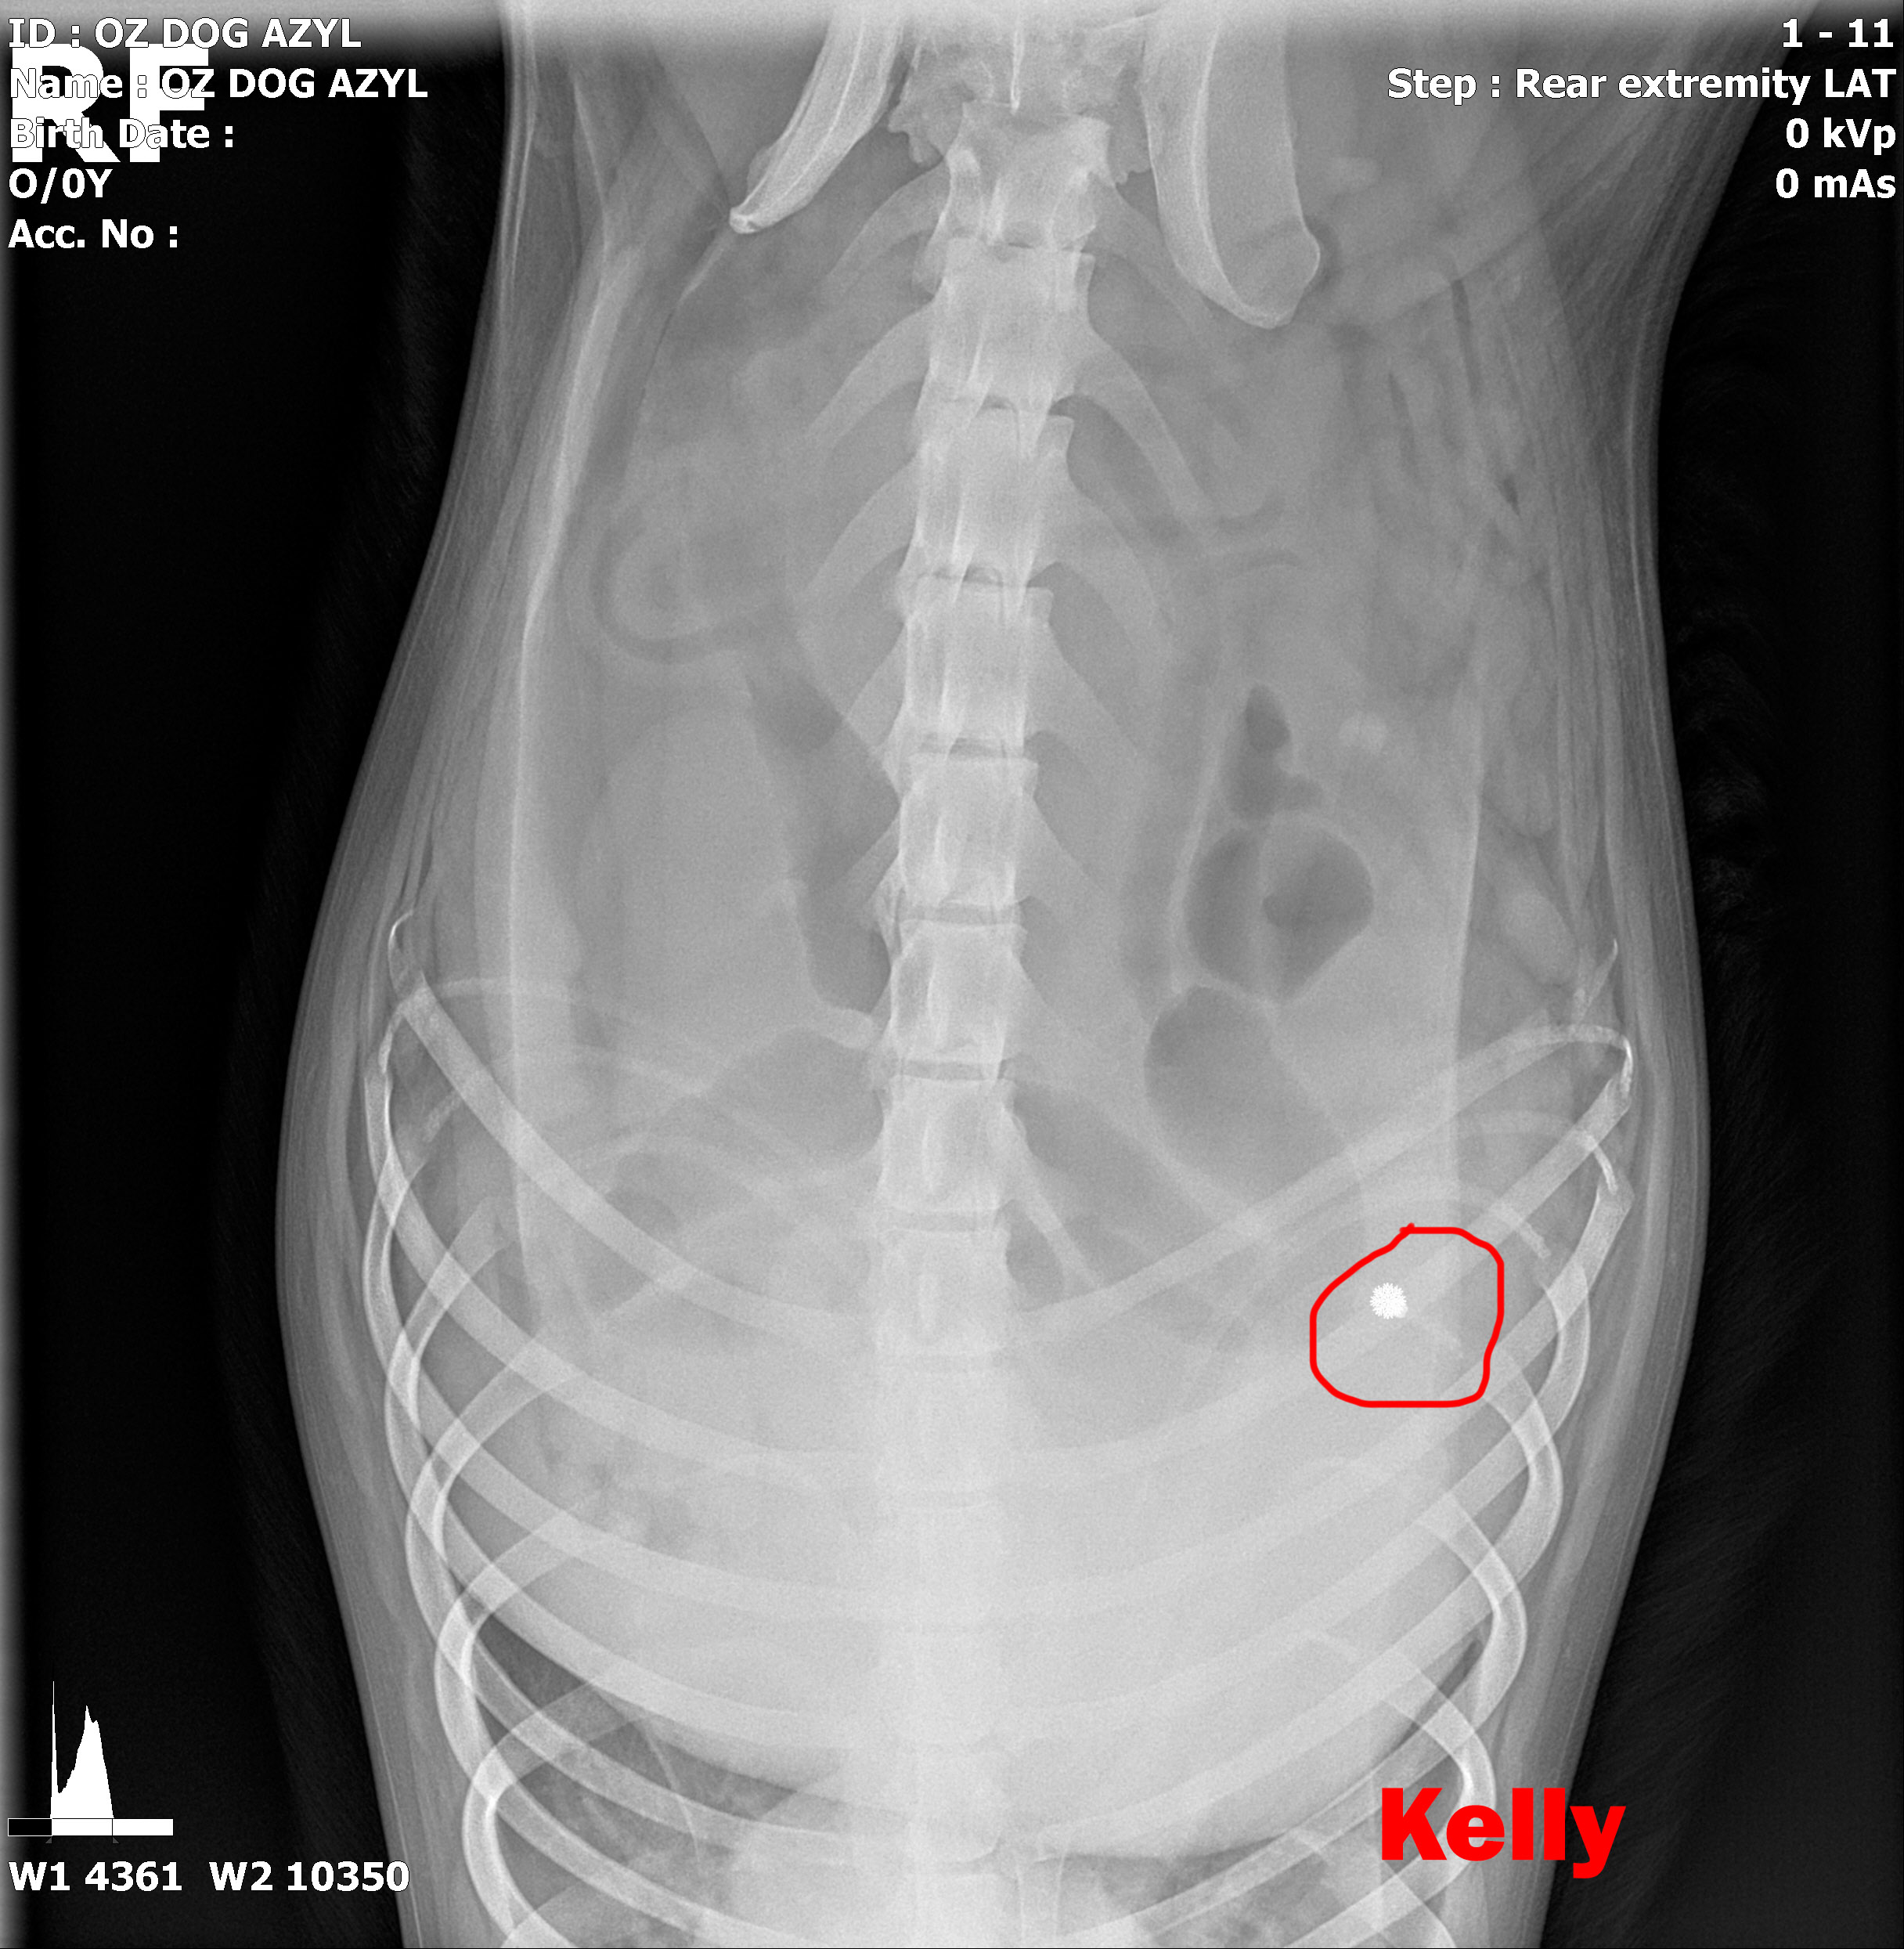

Image removed.KELLY - Vzali sme ju v rámci záchrannej akcie ČSKP z ranča, kde boli zvieratá v hororových podmienkach. Jedli, čo si našli, nekontrolovane sa medzi sebou množili a vôbec nie je vylúčené, že aj na ostatných si nejaký zlomyslený človek skúšal streľbu do diaľky. Kelly je úžasná, pokorná, mierumilovná, oddaná fenka, ktorá sa tak strašne zmierila s utrpením a svojim životom, že celé dni len tíško preleží v peliešku a občas si poplačká. Užíva si každé pohladenie, ale nechce byť nenásytná lebo nevie, či sa jej aj zajtra ujde. Ťažko je ju pohladiť bez toho aby Vám pri nej slza nevytiekla. Nevieme a nechceme si ani len predstaviť akým peklom si musela už prejsť. Kelly má diagnóz hneď niekoľko. Jej primárnym problémom je hrozné krívanie, doslova hopká ako zajko. Neudrží sa na zadných nohách. Môže to spôsobovať hneď niekoľko faktov.

V ľavej packe, medzi druhým a tretím prstom mala brok (treba si to predstaviť, ako keď máte kamienok v topánke a nech stúpate akokoľvek, vždy Vás tlačí. Lenže to je len kamienok a nie cudzí predmet v živom tkanive. Tú bolesť si radšej ani nepredstavujte.) V tej istej nožičke, v oblasti zadnej strany kolena bol ďalší brok, ktorý jej tiež prekážal pri narovnaní nohy. Prvým krokom bolo odstránenie týchto dvoch brokov, ktoré pravdepodobne spôsobovali najväčšie ťažkosti. Operácia sa konala 10.5.2020, dopadla výborne, Kelly sa zotavuje.

Píšeme ale "pravdepodobne" preto, lebo Kelly má tiež problém s krížovým väzom v kolene, ktorý má známky deformácie a má tiež hypointenzitu disku (to znamená, že má na platničke medzi stavcami pruh, ktorý vyčnieva a tlačí na miechu). Veríme, že vsetci strážni anjeli pri nej budú stáť a zvládne sa zotaviť, aby si mohla užívať taký život, aký mala žiť od narodenia. My sme pri nej, zabezpečíme jej všetko potrebné! Za diagnostiku, MRI a chirurgiu máme dve faktúrky, v celkovej výške 762,05€.